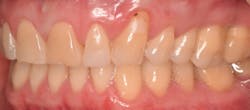

This new biological approach involving blood derivatives A-PRF and I-PRF combined with precision minimally invasive surgery for root coverage demonstrates faster healing without the need of a donor site. The morbidity of GDT is decreased and patient case acceptance is higher compared with traditional grafts. Before-and-after pictures are shown below (figures 15–22).